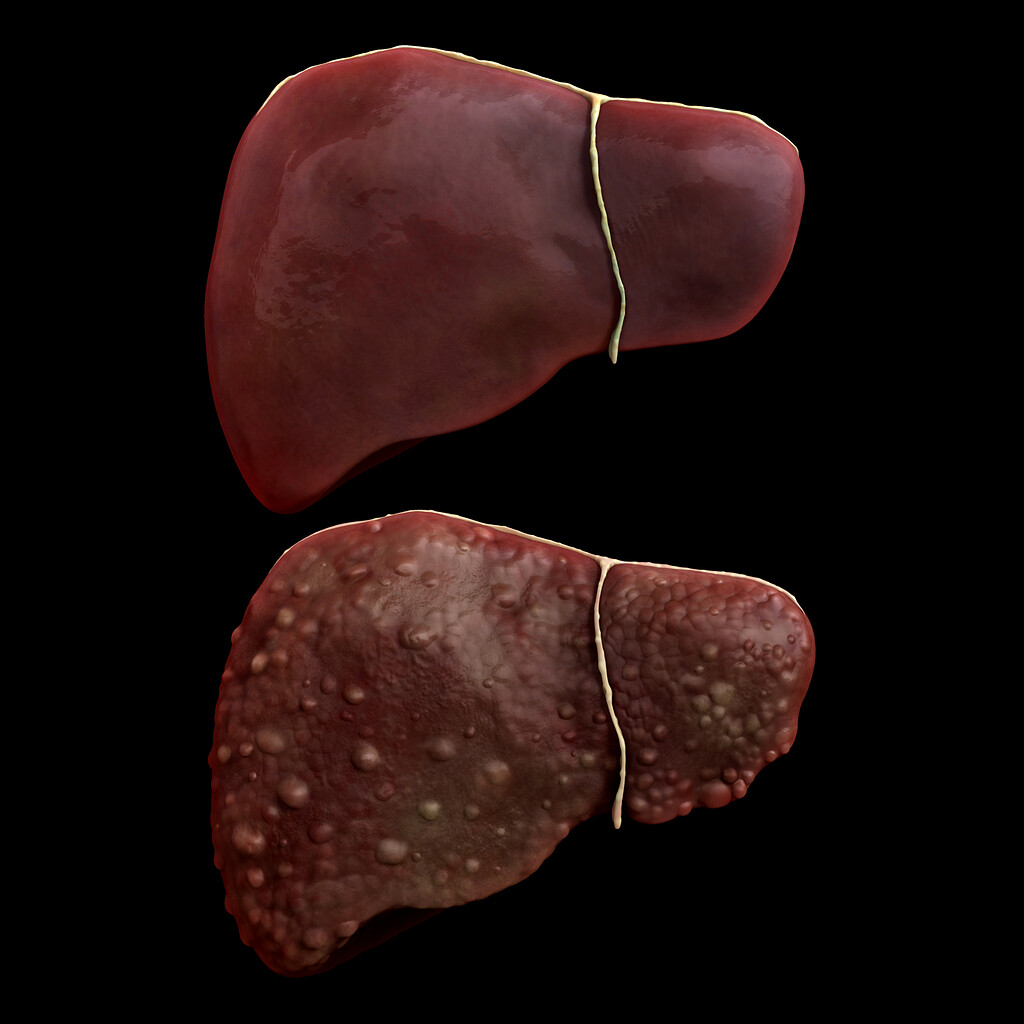

Comparison of a Healthy Liver and one Damaged by Cirrhosis – ZBrushCentral

Comparison of a Healthy Liver and one Damaged by Cirrhosis – ZBrushCentral

Stages of Liver Damage, Illustration – Stock Image – C027/6479 …

Illustration showing a healthy liver (left) and cirrhotic liver Stock …

Stages of liver damage. Starting from a healthy liver (top left Stock …

Normal Liver Versus Liver with Cirrhosis Stock Vector – Illustration of …